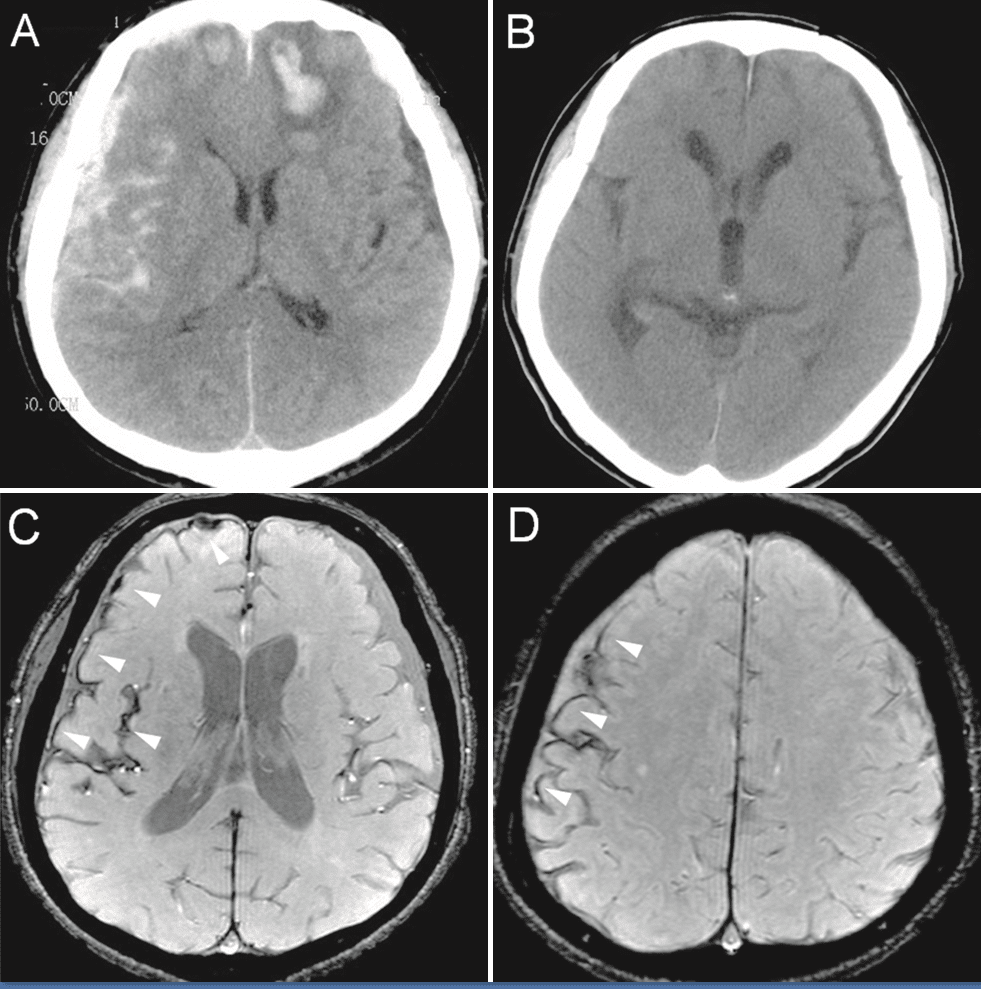

The thoracic is where the stomach is. It’s the foundation, the core. And for that all to be fractured, that’s very serious. She had a scapula fracture, broken ribs, a spleen laceration. She had extensive organic brain damage with numerous bleeds, lesions, permanent structural frontal lobe damage, and brain shrinkage. Her brain got smaller, and memory loss, double vision, inability to control emotions, headaches, dizziness, incontinence, and she needed a cane to walk.

We have to reduce down to 10 million, three past and seven future. And this is a $90 million jury verdict reduced to 10 million. So 80 million just goes poof and disappears. I don’t really get it. The injuries here, the plaintiff suffered anoxic encephalopathy. That means that the brain tissue was damaged by the deprivation of oxygen.

She didn’t get oxygen to the brain and the brain cells, the neurons in the brain, there are 86 billion neurons. They were dying. And once the neurons die, they can’t make connections between the axons and the synapses.

This was a case where a man was brought by ambulance to Kings County Hospital after he was in a hit-and-run car crash. And he was treated for a fractured ankle and a head injury, and he had surgery for his ankle. And then he was hospitalized because he had symptoms of a subdural hematoma. And he was 67 years old.

He was retired and he suffered a stroke. And that stroke left him with permanent injuries and he sued the hospital, claiming medical malpractice in that they failed to timely address the advancing subdural hematoma. That all the clinical signs were there, that the subdural hematomas coming, and they just failed to take care of it.

And the Kings County jury, Kings County by the way is Brooklyn. So it’s Brooklyn. And the jury determined that the hospital did commit medical malpractice by not timely ordering a CAT scan because the CAT scan would’ve shown the subdural hematoma. So it was really simple to find.

So they cut it more than in half. And then the jury also allowed for future medical expenses. That was 7.8 million. And the injuries here were very serious. The plaintiff had functional paraplegia. He also underwent a craniotomy, which is brain surgery. He was admitted for one year to a rehab facility. He needed assistance with daily living, wheelchair bound, cognitive impairments left side contractures.